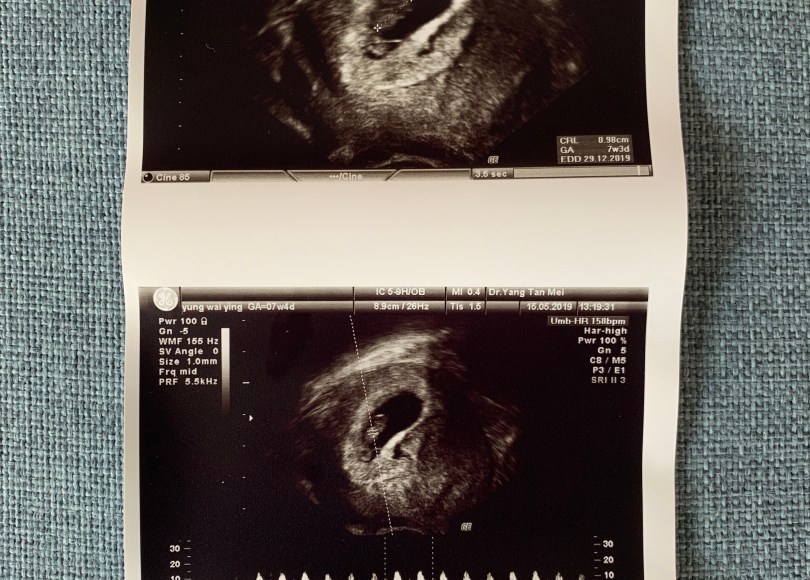

今天雖然有去綵排見了其他人,但沒有特別拍過照,只有幫昨天的超聲波照片拍過照。